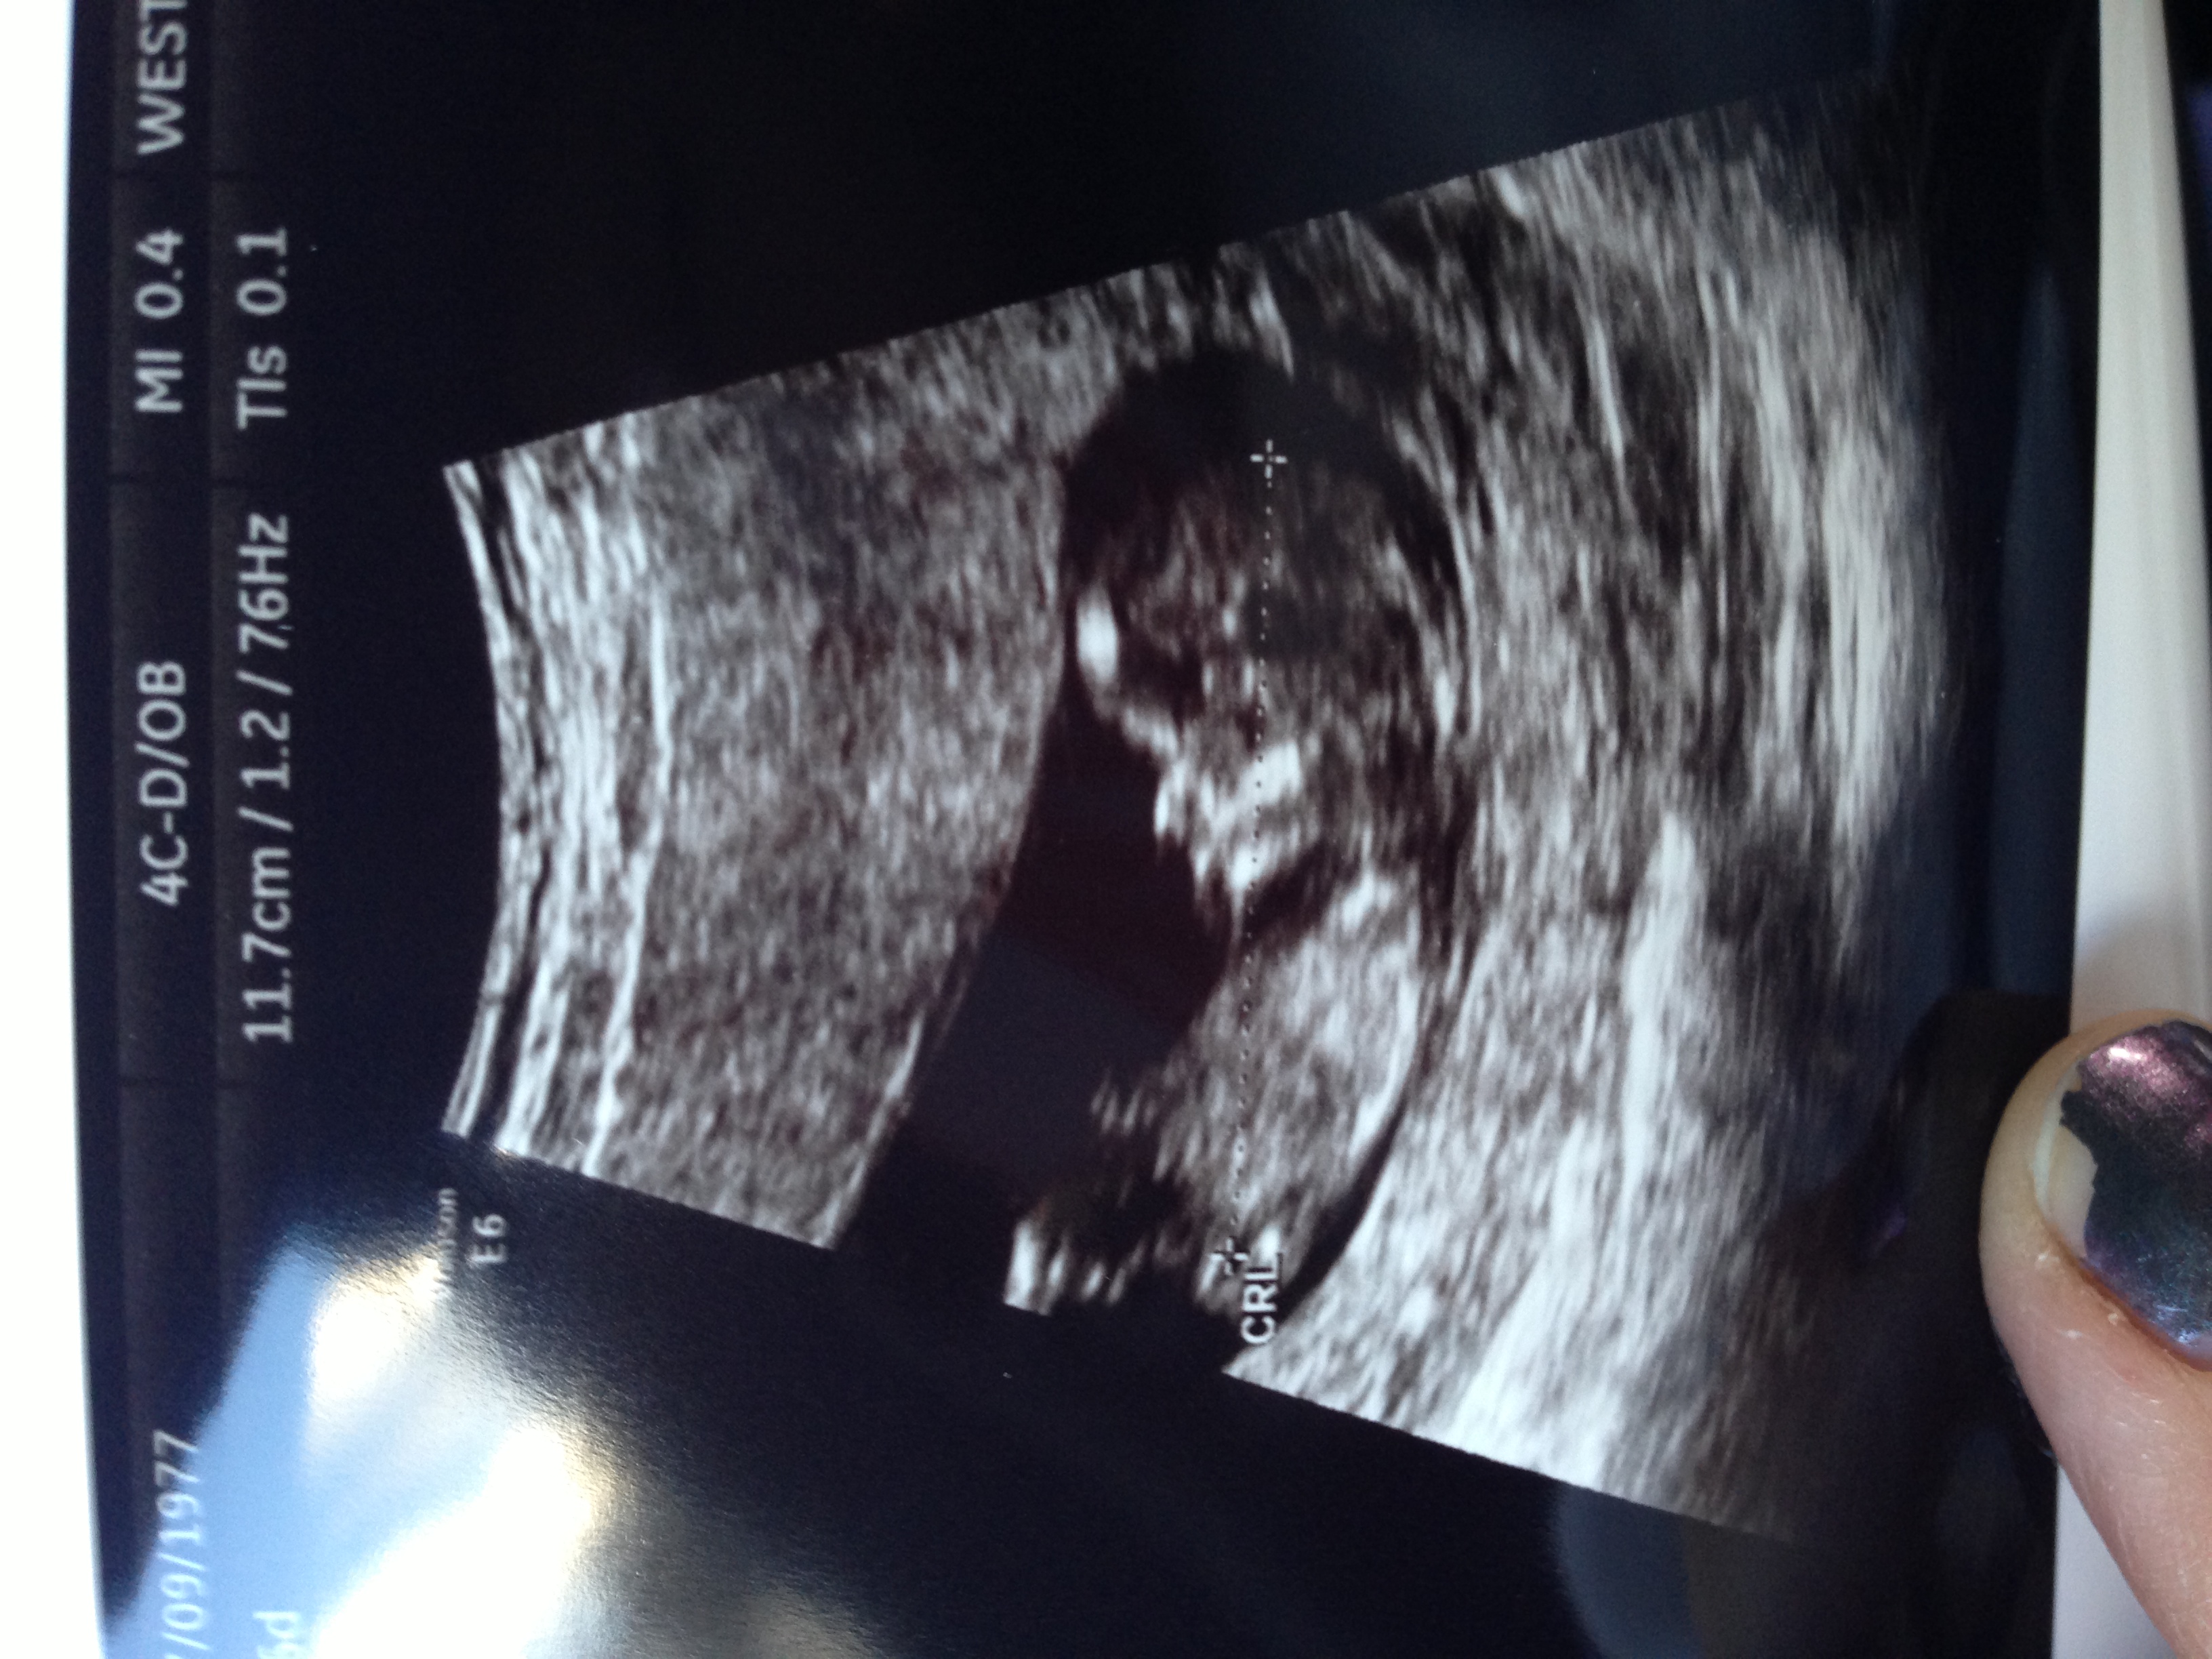

If that a nub I'm guessing girl.

I'm not seeing a nub and skull is just for fun.